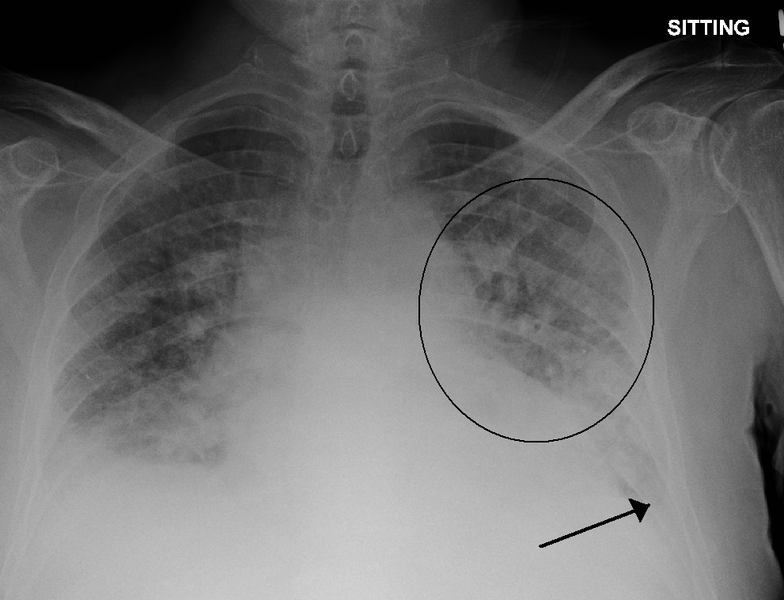

The team of researchers hailing from the MIT Computer Science and Artificial Intelligence Lab (CSAIL) explained that the by detecting signs of excess fluid in lungs (a condition called pulmonary edema), they can determine heart failure severity on a four-level scale with a high degree of accuracy. This particular edema is one of the most outstanding signs of heart failure, and is normally only visible to the expert eye from an X-ray image. Even experts, however, can sometimes miss out on the subtle features necessary to identify the edema. This leads to inconsistent diagnoses, treatment plans, and a pretty chaotic operation.

The CSAIL team solves this problem by developing an AI model that is trained on a massive number of chest radiographs and their associated radiology reports, along with edema severity labels (ranging from 0 to 3, with 3 being the most severe condition). During the inference phase, the model attempts to calculate edema severity from the input image, and even from the given reports.